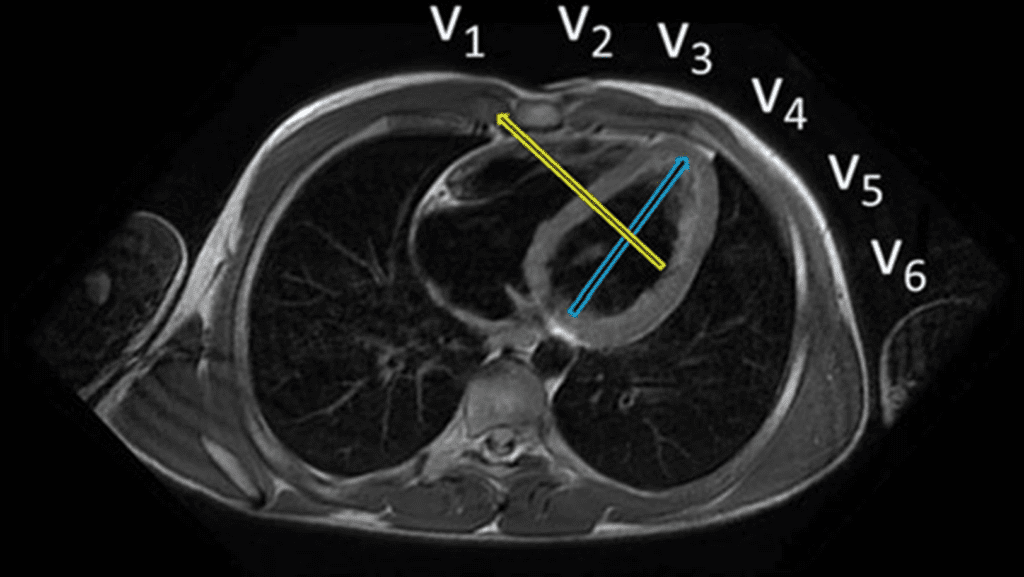

A chamada “parede dorsal” é um dos mitos mais duráveis do ECG. Durante décadas, ensinou-se que certas alterações — especialmente onda R alta em V1–V2 — representariam um infarto da parede posterior (ou dorsal). O problema é que essa parede, do jeito que foi imaginada, praticamente não existe.

O erro nasce de uma premissa anatômica equivocada. O coração não está disposto no tórax como um bloco anterior–posterior. Ele ocupa uma posição oblíqua, e a região antes chamada de “posterior” corresponde, na verdade, ao segmento inferobasal, que faz parte da parede inferior, e não de uma parede independente.

Com o avanço da ressonância magnética cardíaca, esse dogma caiu. Estudos de correlação ECG–RMC mostraram que:

- Onda R aumentada em V1–V2 não indica infarto posterior.

- Esse padrão, quando relacionado a infarto, corresponde mais frequentemente a infarto da parede lateral, cujo vetor de necrose se projeta em direção às derivações direitas.

- Um infarto isolado da suposta “parede posterior” é excepcionalmente raro.

Por isso, a terminologia moderna abandonou o termo “parede posterior/dorsal”. A classificação atual descreve as paredes de forma mais precisa: anterior, septal, lateral e inferior, com seus segmentos basal, médio e apical. O que antes se chamava de “posterior” passou a ser corretamente reconhecido como inferior (inferobasal).